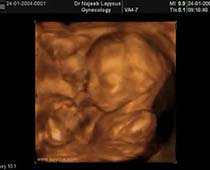

- Fetal Face Ultrasound Photos

- 3D Fetal Profile Ultrasound Scan Photos

- First Trimester Ultrasound Photos

- Multiple Pregnancy Ultrasound Photos

- The Clinical Advantages of 3D and 4D Ultrasound

- Definition and Features of Four Dimensional Ultrasound

- Uses of 4D Ultrasound scan

- The importance of 4D ultrasound imaging in pregnancy